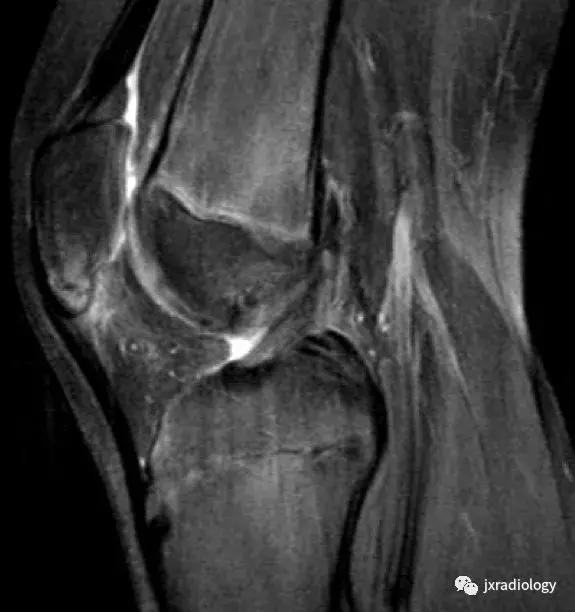

图18:剥脱性骨软骨炎(OCD)。OCD的病因学是未知的,可能是多因素的,包括损伤,血管因素,压力变化,发育差异和遗传学等。膝关节OCD最常见的部位是股骨内侧髁(75%)。这里显示了特征性的MRI表现,通常没有其它的损伤:在骨软骨碎片周围(b)有明显的小片骨髓水肿。(a,b:冠状T1-WI和冠状PD-FS-WI)。

图19:剥脱性骨软骨炎(OCD)。与图18相同的患者。X线片显示右侧股骨内侧髁见骨软骨碎片。